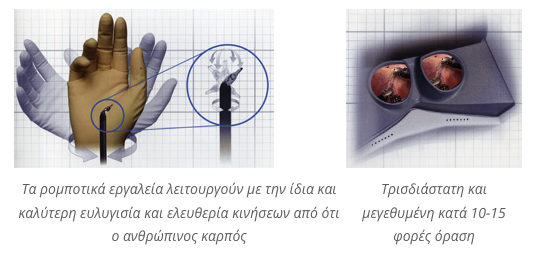

Η ακρίβεια των χειρισμών, η δυνατότητα να υπάρχουν μέσα στην κλειστή κοιλιά του ασθενούς δύο μικροσκοπικά χεράκια που εκτελούν με την ίδια και μεγαλύτερη ευλυγισία και ελευθερία τις κινήσεις του ανθρώπινου καρπού, η μεγεθυμένη και τρισδιάστατη εικόνα και ο έλεγχος που παρέχει το ρομποτικό σύστημα da Vinci συμβάλει στην αφαίρεση του προστάτη, που έχει προσβληθεί από καρκίνο, διατηρώντας ταυτόχρονα τα σπουδαία στυτικά νεύρα και αιμοφόρα αγγεία.

Η κοιλιά γεμίζει με το αδρανές αέριο διοξείδιο του άνθρακα δημιουργώντας έτσι ένα μεγαλύτερο χώρο εργασίας στον χειρουργό για να ολοκληρώσει την επέμβαση. Αυτό το αέριο εκκενώνεται από την κοιλιά στο τέλος του χειρουργείου. Ο χειρουργός χειρίζεται 3 πολυ-αρθρωτά όργανα για να φέρει σε πέρας με ακρίβεια, λεπτότητα και σταθερότητα το δύσκολο έργο του διαχωρισμού των ιστών, της αιμόστασης, της κοπής και συρραφής με την ίδια και ανώτερη δεξιότητα από εκείνη του ανθρώπινου καρπού.

Πολυ-αρθρωτά ρομποτικά εργαλεία επιτρέπουν στον ουρολόγο μέσα στο σώμα του ασθενή με την ίδια ικανότητα σαν να έχει δύο μικροσκοπικά ανθρώπινα χέρια.

- Πρώτον, υπάρχει βελτιωμένη όραση με 10-15 φορές μεγέθυνση και μία υψηλής ευκρίνειας εικόνα της εσωτερικής ανατομίας σαν αποτέλεσμα χρήσης μίας εξειδικευμένης στερεοσκοπικής οπτικής, η οποία είναι συνδεδεμένη με μία υψηλής ευκρίνειας κάμερα.

- Δεύτερο, ο ρομποτικός ουρολόγος χειρουργεί με πολυαρθρωτά όργανα, διαμέτρου 8 χιλιοστών, τα οποία έχουν την ίδια δεξιότητα όπως ο ανθρώπινος καρπός.

Τα λεπτά πολυ-αρθρωτά εργαλεία του συστήματος da Vinci, που μοιάζουν σαν μικρά ανθρώπινα χεράκια, έχουν πολύ μεγαλύτερο εύρος κινήσεων απ’ ότι ο ανθρώπινος καρπός. Το ρομποτικό σύστημα da Vinci φιλτράρει άμεσα κάθε τρέμουλο των χεριών του χειρουργού και κάνει τις κινήσεις πιο πλαστικές και κλιμακωτές δίνοντας περισσότερη βαρύτητα στην ακρίβεια και και στην φυσική ροή της κίνησης των ρομποτικών εργαλείων.

Τα ρομποτικά εργαλεία του συστήματος da Vinci έχουν την διάμετρο ενός μολυβιού.

Η υψηλής ευκρίνειας τρισδιάστατη όραση και η μεγέθυνση 10-15 φορές επιτρέπουν στον χειρουργό να βλέπει και τον καρκίνο και τους υγιείς ιστούς και τα αιμοφόρα αγγεία σε τέτοιο επίπεδο μεγέθυνσης και λεπτομέρειας που είναι πολύ ανώτερο από εκείνο που προσφέρει η ανοιχτή χειρουργική ή η συμβατική λαπαροσκοπική χειρουργική.

Η υψηλής ευκρίνειας τρισδιαστατη και μεγεθυμένη όραση δίνει την εντύπωση “κατάδυσης στον εσωτερικό κόσμο” του ασθενούς!